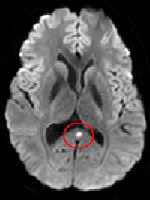

Aneurysm of Right Sinus of Valsalva: A Particular Case Report and Brief Review of Literature

LUIGI NUNZIATA, Saverio Ambrosino, Mario Volpicelli, Michele Capasso, Luigi Caliendo

International Journal of Innovative Research in Medical Science·February 14, 2023